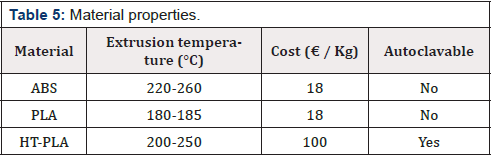

Because of the dimension of this particular bone (X = 91.34 mm, Y = 372 mm and Z = 77.58 mm) (Figure 16), MeshMixer is used to separate the geometry in two parts and generate a connection pin (Figure 17). The 3D printer used for this application is an FDM (Fused Deposition Modeling) technology, EZT3D Delta (Figure 18). In (Table 5) a material cost analysis was carried out based on the current price on market of the specific material per kg. Moreover, the autoclavability was considered despite the cost because of the particular medical application. Finally, the methodology studied, allowed to obtain a three-dimensional bone model in PLA that perfectly fits the anatomical structure of the CT images (Figure 19).

Cost Analysis

The realization of the three-dimensional model involves a series of costs:

1. Purchase of the 3D printer

2. Labor cost

3. Material cost

4. Software

The costs relative to this specific printed model are summarized in (Table 5). The cost of the printer is about 220 € and its useful life is approximately of 2000 working hours. The labor time required for the conversion and the cleaning of the model is 4 hours average and the estimated cost of the specialized operator is 20 €/h. For the printing of the model it is necessary an average of 0,250 kg of material. The actual printing time to get the 3D model is 22 hours. The software used in the proposed procedure are all open source and they don’t imply added costs.